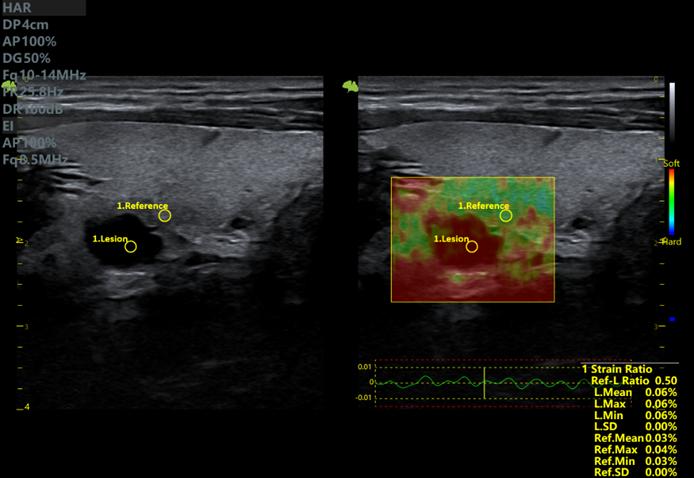

5. Giải pháp hình ảnh tổng quát: EI (Hình ảnh đàn hồi mô nén)

Một kỹ thuật không xâm lấn, thời gian thực đo độ cứng của mô để phát hiện sớm các dấu hiệu ung thư, giảm số lượng sinh thiết và theo dõi xơ hóa trong bệnh gan mãn tính. Kỹ thuật này đặc biệt hữu ích cho việc đánh giá vú, gan, tuyến giáp, tuyến tiền liệt và hệ cơ xương khớp.

Công nghệ đàn hồi mô trên Vinno